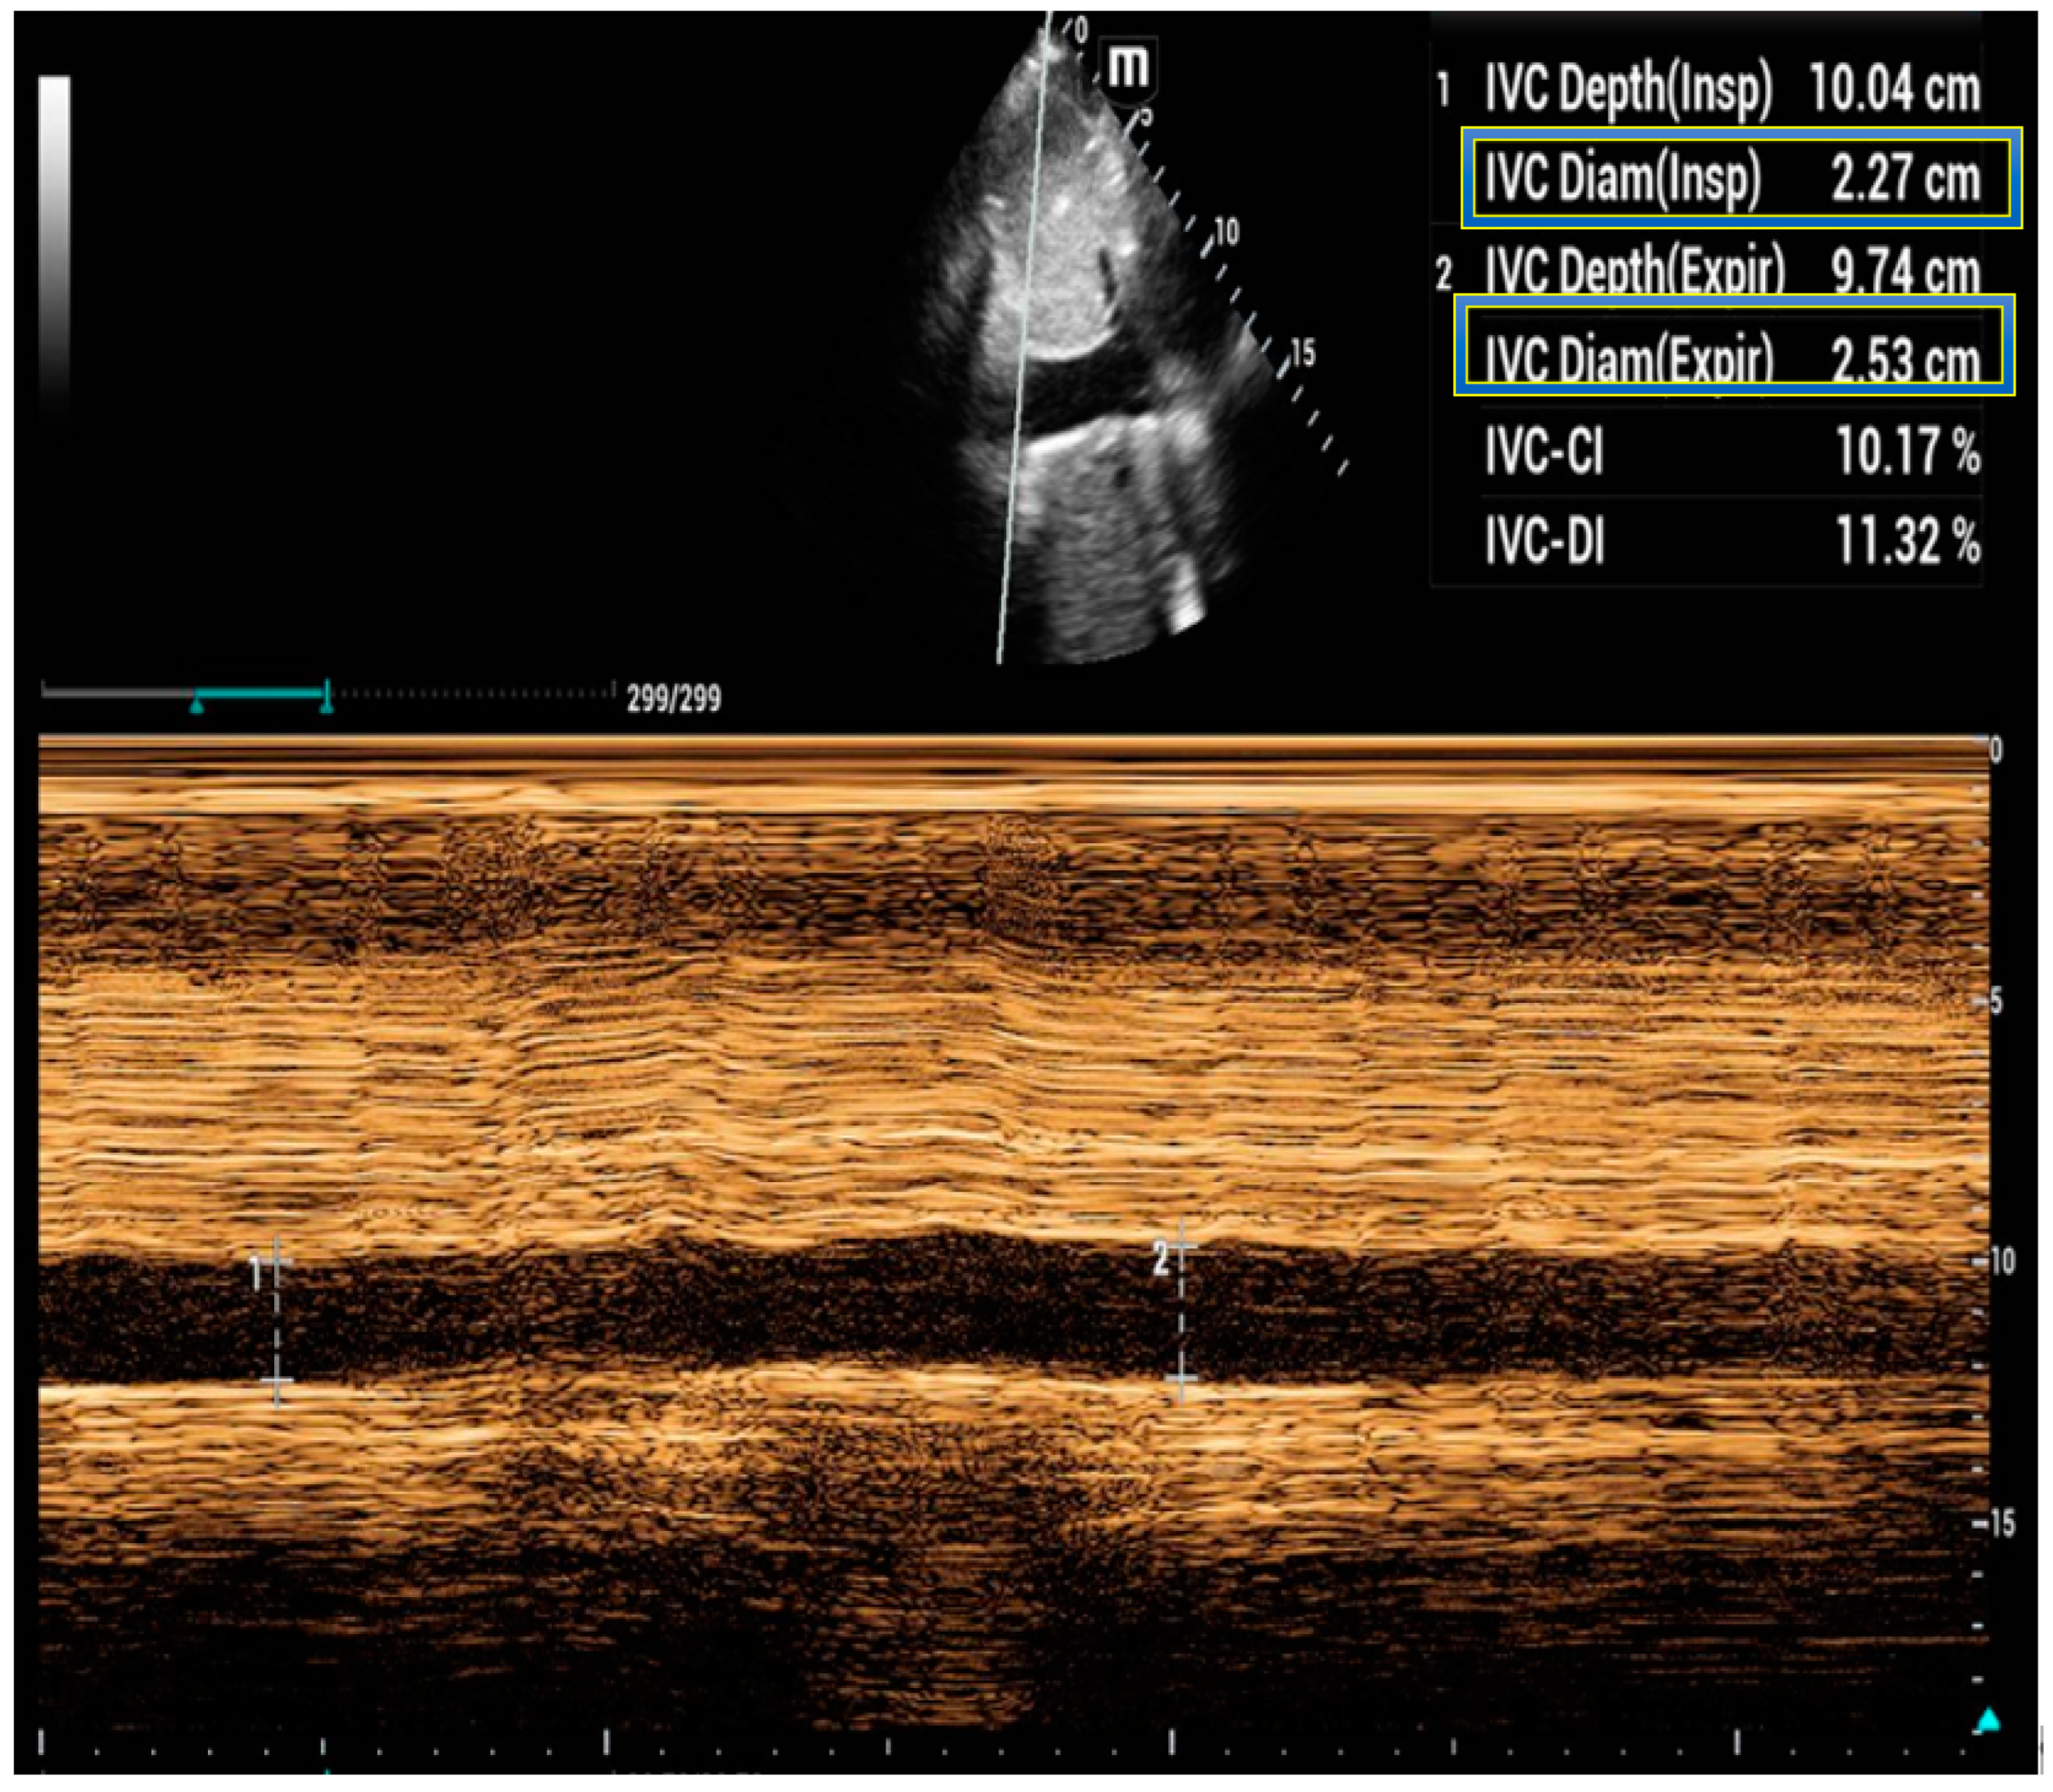

5. Inferior Vena Cava Ultrasound